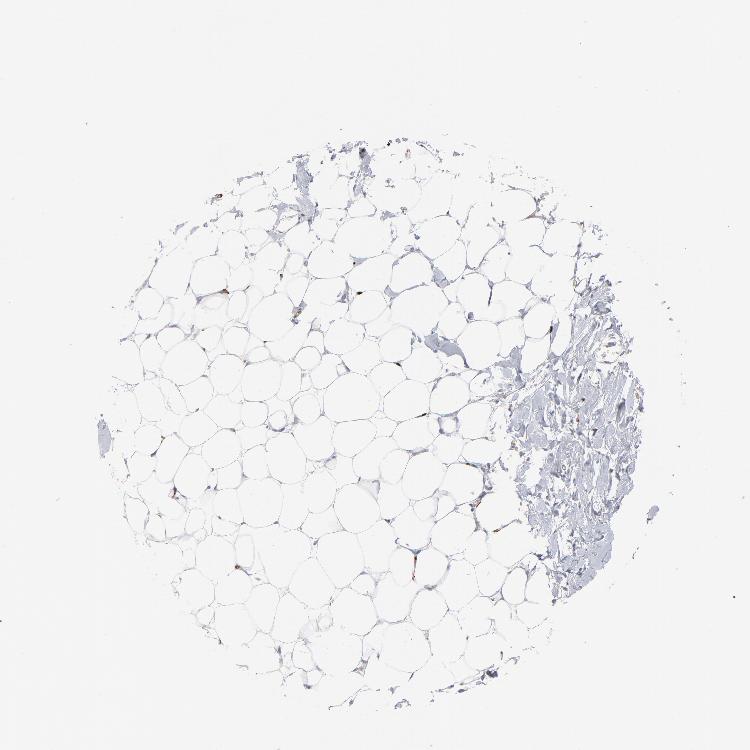

BREAST - Antibody stainingi

Antibody staining in the annotated cell types in the current human tissue is reported as not detected, low, medium, or high, based on conventional immunohistochemistry profiling in selected tissues. This score is based on the combination of the staining intensity and fraction of stained cells.

Each image is clickable and will lead to virtual microscopy that enables deeper exploration of all samples and also displays staining intensity scores, fraction scores and subcellular localization as well as patient and tissue information for each sample.

Antibody CAB003795

Adipocytes Not detected

Glandular cells Not detected

Myoepithelial cells Not detected